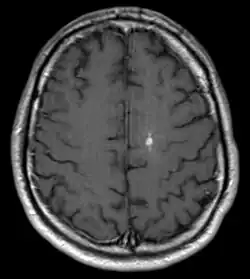

DVA in der Magnetresonanztomographie: T1 mit Kontrastmittel axial

Bei der Developmental Venous Anomaly (DVA) handelt es sich um eine gutartige, venöse Fehlbildung im Gehirn, die in den meisten Fällen symptomlos bleibt. Im typischen Fall zeichnet sich die Anomalie durch einen Strauß erweiterter, medullärer Venen aus, die auf eine kaliberstarke zentrale Drainagevene konvergieren. Die Venen sind an der normalen Drainage des Hirngewebes beteiligt, so dass ein Verschluss zu einer hämorrhagischen Infarzierung führen kann. Oft werden DVAs zufällig bei einer Magnetresonanztomographie des Gehirns entdeckt. Sie können jedoch auch mit anderen Gefäßfehlbildungen wie z. B. Kavernomen assoziiert sein.